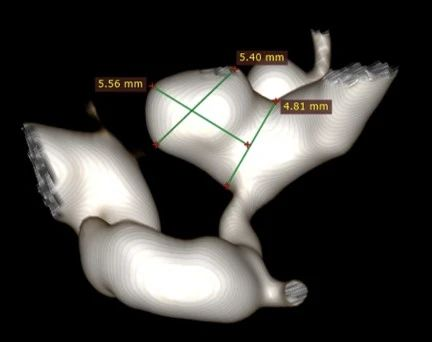

4. 3D重建后我们可以看到,这是一个宽颈的分叶状动脉瘤,载瘤动脉正常管径大约4mm左右,但狭窄段最细仅有1mm多,支架的选择至关重要。

3D重建与测量